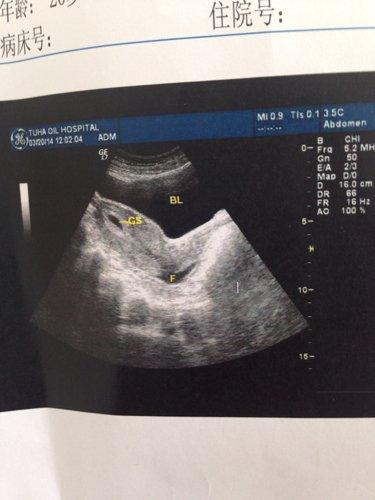

子宫前位,大小约58x49x32mm,形态饱满,肌层回声均匀,宫腔内见16x13x8mm的厚壁双环

子宫前位,大小约58x49x32mm,形态饱满,肌层回声均匀,宫腔内见16x13x8mm的厚壁双环囊状回声,未见胚芽及原始心管搏动,孕囊周边可见10X6mm无回声,宫颈前后26mm,内未见明显占位。子宫肠窝可见34x10mm的无回声。我想问我怀孕多长时间

病情分析: 你的情况考虑根据孕囊情况,考虑怀孕应该在34天左右的情况,注意休息的 指导意见: 考虑检查结果伴随积液的情况预防先兆流产的可能,建议定期到医院检查胎儿的情况较大,同时建议应该用药复查多喝水